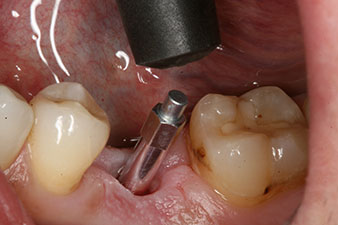

The torque used for the machine-driven placement was 43 Ncm. In addition, after screwing a measuring post (SmartPeg) specially matched to the implant, the ISQ value was measured with the probe of the W&H Osstell ISQ module.

This module is an optional extra for the W&H Implantmed and is docked to the implantology motor (see Fig. 11). The dimensionless ISQ value immediately after insertion was 64 orovestibular and 68 mesiodistal (maximum value = 100).